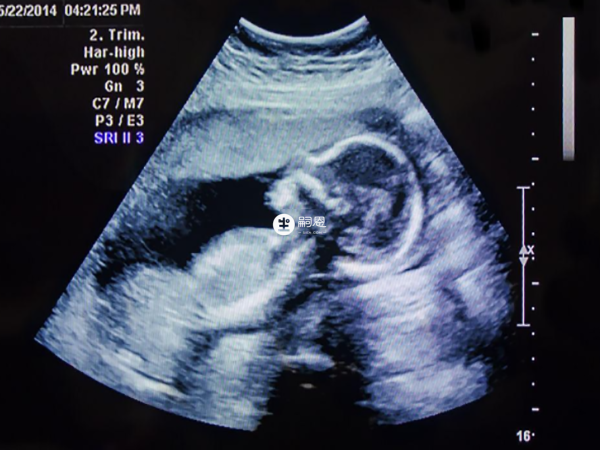

看四維彩超單子,必須是照到胎兒寶寶的下半身,如果彩超影象有突出的東西,像一團菌狀,有時候可能出現3個亮點,那代表可能懷男孩,如果彩超影象有三條線的標誌,那代表可能懷女孩,這個方法和看影象一樣,都不是特別準確。

如果做四維剛好從下往上拍到寶寶生殖器官的部位,那麼彩超影象上有三條線的標誌,代表可能懷女孩,如果彩超影象上有三個亮點,那麼代表可能懷男孩。